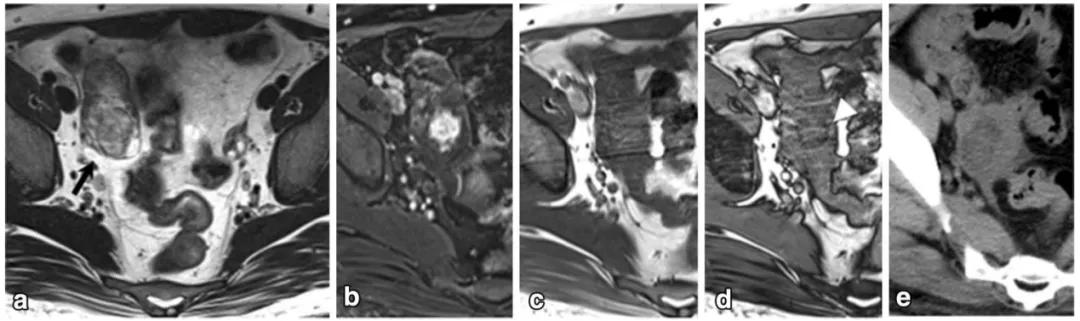

女,47 岁,卵巢子宫内膜样癌。右侧卵巢异常信号肿物,T2WI 混杂稍高及高信号(图 a),DWI 高信号(图 b),增强扫描不均匀强化(图 c)。肿物内见条片状裂隙样异常信号(箭头),T2WI 呈高信号、DWI 低信号、增强扫描未见强化。

女,64 岁,雌激素升高,卵巢子宫内膜样癌。卵巢肿物由三部分构成,偏右侧是囊性成分;中间部分(箭头)T2WI 及 DWI 呈低信号(a 及 b),增强扫描明显强化(c 增强早期,d 增强晚期);偏左侧部分 T2WI 稍高信号,DWI 高信号,增强扫描明显强化。HE 染色显示中间部分肿物由功能性纤维间质构成(图 e)。HE 染色肿瘤左侧部分显示子宫内膜样癌与性索间质肿瘤类似。矢状位显示子宫体积增大(图 g)

女,75 岁,浆液性癌。CA-125 升高。双侧卵巢不规则肿物,与腹膜结节分界不清,T2WI 呈不均匀稍高信号(图 a),DWI 呈不均匀高信号(图 b),CT 显示肿物内钙化(图 c)。箭头显示左侧髂血管旁转移淋巴结。

女,61 岁,雌激素升高。MR 显示左卵巢实性肿物,T2WI 呈稍高信号(图 a),内部多发小囊变(白箭),DWI 呈高信号(图 b),增强扫描明显强化。T2WI 显示子宫腺肌症(箭头)。

女,22 岁,无性细胞瘤。乳酸脱氢酶及碱性磷酸酶升高。T2WI 示右侧卵巢分叶状肿物(图 a),DWI 呈高信号(图 b),增强扫描明显强化(图 c)。箭头显示肿物内可见纤维血管分隔。